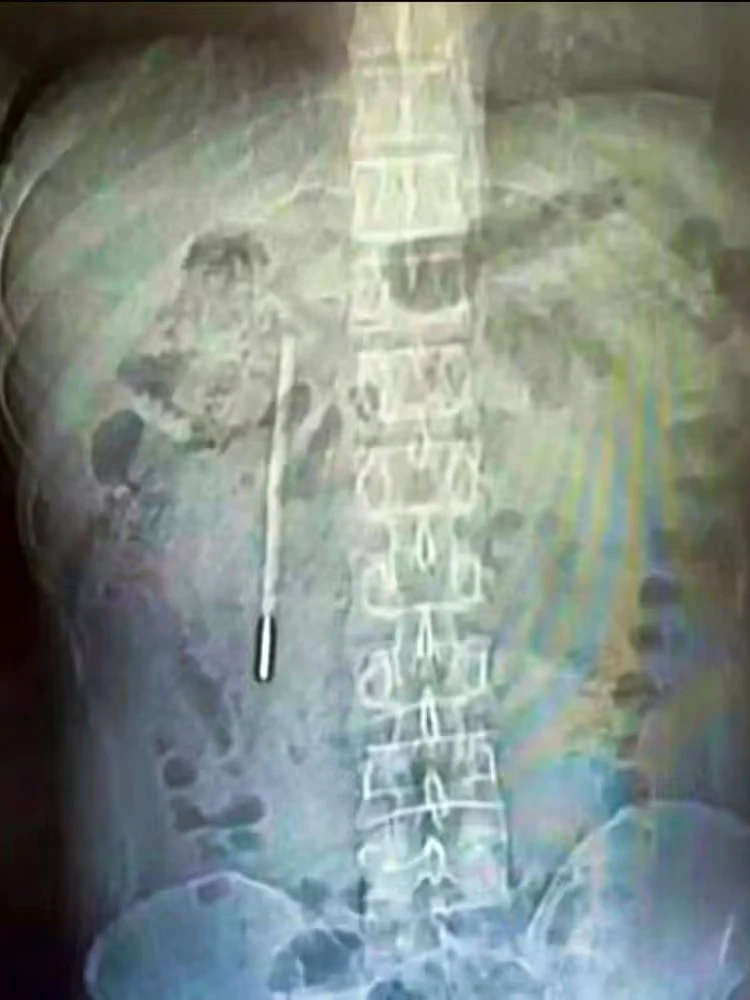

Der Mann hatte über anhaltende Bauchschmerzen geklagt, woraufhin Untersuchungen schließlich einen Fremdkörper im ersten Abschnitt des Dünndarms, dem sogenannten Duodenum, zeigten: ein Thermometer.

Das Gerät hatte sich so im Körper positioniert, dass es direkt gegen die Darmwand drückte. Dadurch bestand akute Gefahr von Verletzungen und inneren Blutungen. Die Ärzte reagierten rasch und entfernten den Fremdkörper im Rahmen eines rund 20-minütigen Eingriffs erfolgreich.

Mann lebte 20 Jahre lang mit Thermometer im Bauch

Weibo